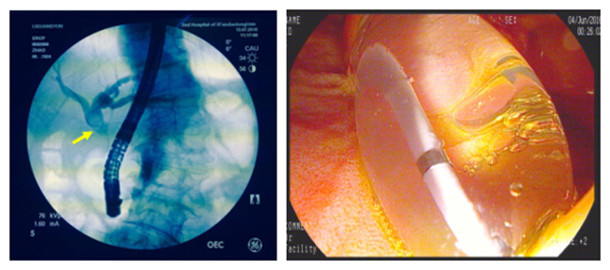

2016年7月13日,由赵刚主治医师操作,在左爱丽护士长、李婵护士、杨龙宝博士的协助下,在密切监护患者生命体征的同时对其实施ERCP手术。术中可见患者十二指肠降部有多发巨大憩室,十二指肠乳头位于其中一憩室内,属于憩室内乳头的情况,操作稍有不慎即可能引起十二指肠穿孔。一次性顺利插管至胆总管并造影,确认了胆管中结石的大小约1.2cmx1.4cm,位于肝总管处(结石可能由于插管及造影发生了位移),同时也发现由于憩室的压迫,患者胆管走形异常扭曲。我们对该患者的十二指肠乳头进行了小切开并以1.2cm胆管扩张球囊进行扩张,后以取石球囊顺利自胆管中取出巨大成型结石一枚,再次造影胆管内未见残存结石,遂置入鼻胆管,整个操作过程用时仅30分钟。患者术后第2天即恢复正常饮食,腹痛症状基本消失,目前已经顺利出院。

十二指肠乳头位于一巨大憩室内(黑箭头所示为憩室)

造影可见结石位于肝总管处(黄箭头所示) 胆道扩张球囊进行扩张的过程